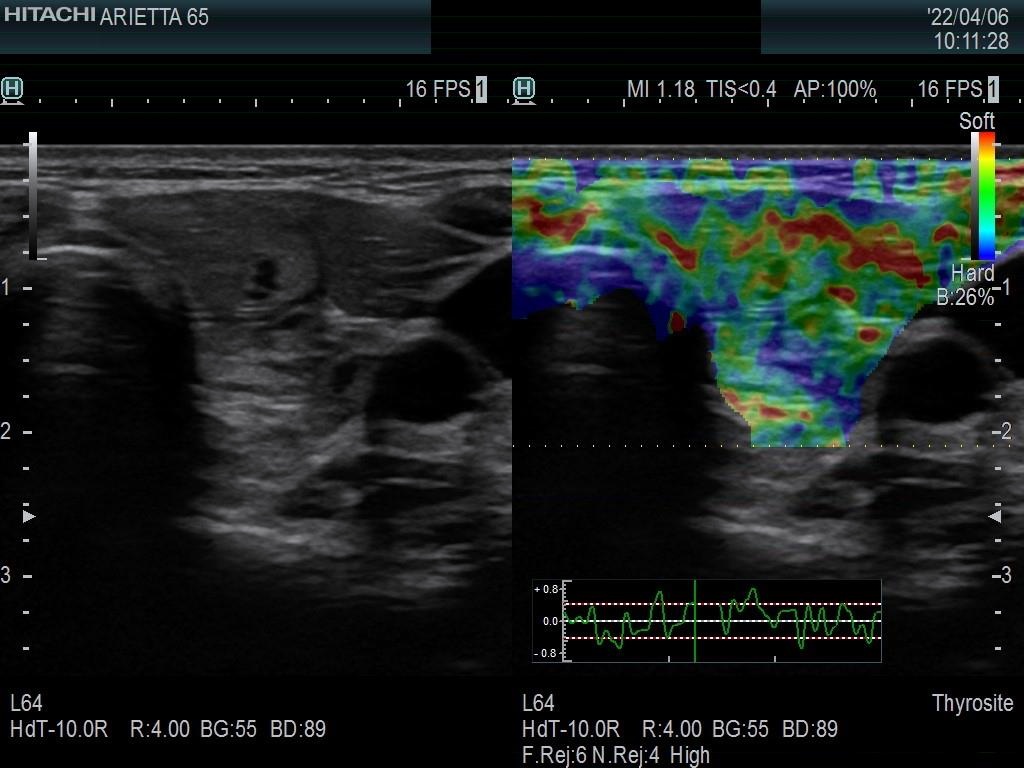

Ultrasonography. The thyroid was moderately hypoechoic and presented with numerous more and less hypoechoic discrete lesions. The largest of the latter was in the lower ventromedial part of the left lobe and had cystic areas and intranodular echogenic figures. The latter included typical comet tail artifacts, back wall cystic figures and some ambiguous small bright granules. The lesion showed both perinodular and intranodular vascularity. Compared with the former examination the nodule increased by 22% in volume. This difference is within the intraobserver variation.

Comment. Based on the presence of typical comet-tail artifacts, the questionable punctate echogenic granules are worth considering also colloid crystals.